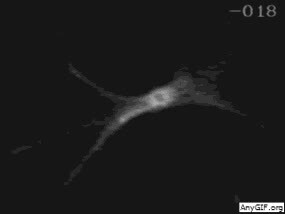

6、T细胞的“死亡之吻”

细胞毒性T细胞(也被称为“杀手T细胞”)正在识别受病毒感染、癌变之类的“不正常细胞”,导致细胞死亡。整个动图实际用时约为75分钟。